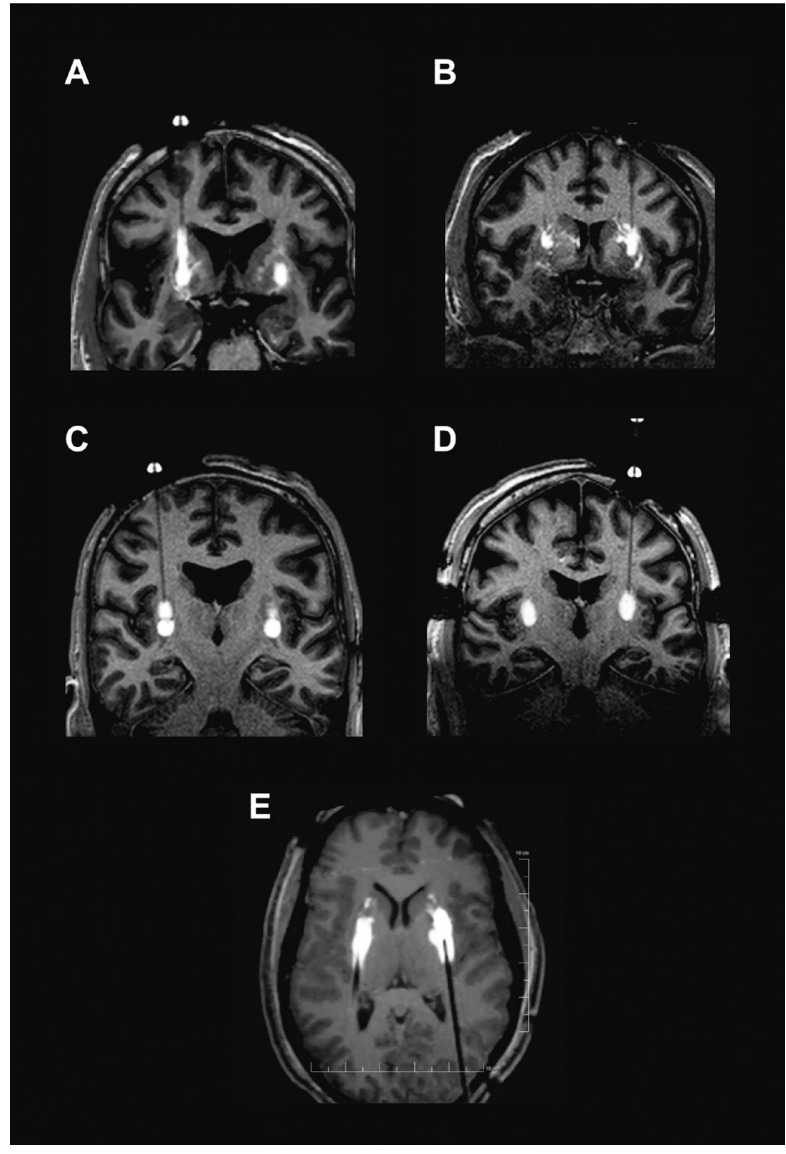

Figure #29 below seeks to visually confirm the distribution of the drug via cannula administration to the brain. Images showcase results from the PD-1101 trial of backflow (Image A), perivascular leakage (Image B), stacked infusions (Image C), and progressive stepped advancement administration (Image D).

Figure #29: MRI images showcasing intraoperative monitoring of the administration of a viral vector mixed with gadoteridol (contrast) into Parkinson’s Disease patients

A - Backflow up cannula track

B - Perivascular and off-target leakage

C - Stacked infusions

D - Progressive stepped advancement